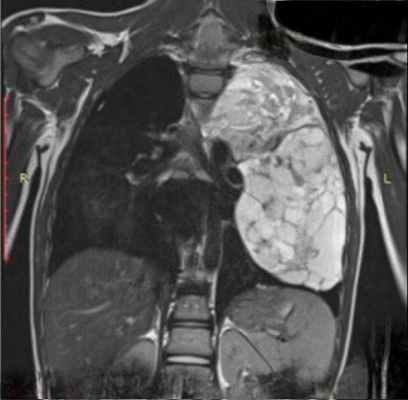

На рентгенограммах интенсивное, гомогенное затемнение правого легочного поля от I ребра до диафрагмы со смещением пищевода, сердца и сосудов влево.

Пульс 78 ударов в минуту, ритмичный. Артериальное давление 125/80 мм. На электрокардиограмме диффузные изменения миокарда. Периферические лимфатические узлы не увеличены. Анализы крови и мочи без особенностей.

С диагнозом кисты средостения под местной анестезией произведена торакотомия справа в шестом межреберье с пересечением хрящей реберной дуги. Плевральная полость почти полностью заполнена громадной мягковатой опухолью темного цвета. Произведено частичное удаление опухоли путем кускования. Тщательный гемостаз.

В послеоперационном периоде отмечалась пневмония, гемоторакс. Больная выписана через 3 недели после операции в удовлетворительном состоянии.

Гистологическое исследование опухоли показало наличие гемангиоэндотелиомы. Среди значительно ослизненнои соединительной ткани отмечается обилие кровеносных сосудов разного калибра, преимущественно капиллярного типа. Встречаются и более крупные сосуды с утолщенной стенкой, напоминающие так называемую гипертрофическую ангиому. Местами скопление несколько вытянутых клеток эндотелия (П. Н. Васильев).

Больная умерла через 7 месяцев после операции в результате продолжающегося роста опухоли и сдавления жизненно важных органов.

В данном случае можно было отметить исключительно бурный рост опухоли, достигшей за короткий срок громадных размеров, но не сопровождающейся метастазированием.